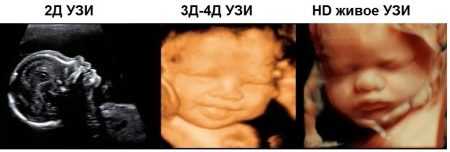

Выделяют 3 вида ультразвукового исследования: обычное, 3D и 4D. Каждый тип имеет свои отличительные качества, особенности, преимущества. Во время беременности женщина проходит обследование на аппаратах с разной визуализацией. Например, на ранних стадиях беременности запрещено использовать 3Д и 4Д УЗИ, поэтому акушер-гинеколог назначает обычное.

2Д, или обычный, ультразвук помогает получить двумерную черно-белую картинку. Положение ребенка отображается в двух измерениях – по высоте и по длине. С его помощью обследуются внутренние органы плода, околоплодные воды, определяется динамика развития ребенка. 2D УЗИ делится на 2 вида:

3D

Поможет увидеть объемное изображение с 3D визуализацией, на мониторе будет отображаться трехмерная картинка, что позволит хорошо рассмотреть плод. Назначается с 20 по 33 неделю беременности, когда сформировались внутренние органы ребенка. Длится обследование 45 минут, позволяет определить наличие патологий, рассмотреть плод независимо от его положения.

4D

4Д позволяет не только увидеть, но и услышать ребенка, его сердцебиение, звуки. На монитор поступает не изображение, а видео. Обследование можно записать на диск или на другой накопитель, получив на память фильм о внутриутробной жизни ребенка. Назначается с 15 по 33 неделю беременности, длительность обследования – от 1 часа. 4D не наносит вреда плоду, сила, интенсивность ультразвуковой волны приравниваются к обычному ультразвуковому исследованию.

С развитием технологий в центрах планирования семьи и частных клиниках взамен уже привычного двухмерного УЗИ все чаще используются 3D-аппараты, дающие объемное изображение (помогает лучше оценить анатомию плода) и даже 4D (движущееся объемное изображение).